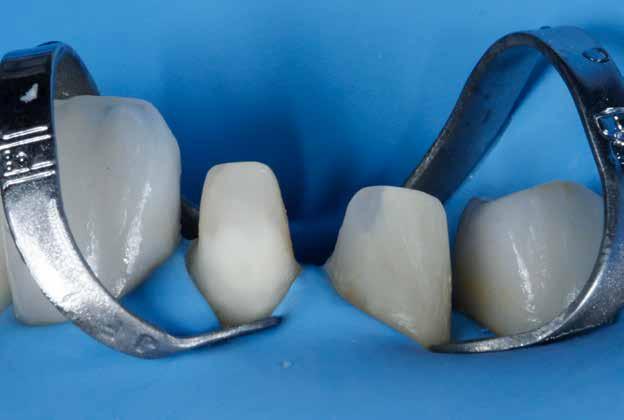

A szakirodalomban fellelhető eredmények alapján kerámia héjak ragasztására a kontaminációtól mentes, frissen vágott zománc felszín a legalkalmasabb. A hosszú távú sikeresség elérésének további feltétele a fogak konzervatív módon történő preparálása, továbbá a ragasztás kofferdám felhelyezésével biztosított, abszolút izolálásban történő kivitelezése. Úgy véljük, hogy a fenti faktorok biztosították a cikkben bemutatásra kerülő esetek – 5 évvel az átadás után megfigyelhető – sikerességét. A kofferdám izolálás alkalmazása számos előnyt biztosít a gyakorló fogorvos számára. Megakadályozza a munkaterület nyállal, vérrel, vagy szulkusz-váladékkal történő kontaminációját, és javítja a kezelendő területre való rálátásunkat. A fogak kerámia héjak ragasztása előtt történő izolálása azonban gyakran kihívást jelenthet a kevesebb klinikai tapasztalattal rendelkező fogorvosok számára. Jelen esetbemutatásban ismertetjük a kofferdám felhelyezésének lépéseit és néhány olyan gyakorlati tanácsot, amelyek jelentősen megkönnyíthetik a munkánkat, azokban az esetekben, amikor a második kisőrlőfogak közti területet kívánjuk kofferdám segítségével izolálni. A kofferdám kapcsok segítségével került rögzítésre, majd fogakat körülvevő széleit óvatosan az ínybarázdába forgattuk. A kerámia héjak számára előkészített fogakra ragasztás előtt egyenként kapcsokat helyeztünk annak érdekében, hogy a kerámia héjak rögzítése ideális körülmények között történhessen. A lépések részletes ismertetése segítséget jelenthet – a kevesebb klinikai tapasztalattal rendelkező fogorvosok számára – az abszolút izolálás megvalósításához szükséges lágyrészmenedzsment megértéséhez. Ezek az ismeretek rendkívül hasznosak lehetnek, ha a jövőben a kerámia héjak ragasztását megfelelő módon megvalósított kofferdám izolálás mellett kívánják kivitelezni. A cikkben ismertetett módszerek alkalmazásával az abszolút izolálás megvalósítható, a gumilepedő – vérzés nélkül – ínybarázdába történő beforgatására, és a ragasztáshoz szükséges idő csökkentésére.

Az előzetes állapotfelmérést és a kezelés megtervezését követően a fogakat minimál invazív módon preparáltuk (1. a-b ábrák), majd az előkészített fogak ínybarázdáiba fonalbehelyező eszköz segítségével (113 Serrated Gingival Cord Packer, Hu-Friedy, Chicago, Illinois) teflonszalagot helyeztünk (Loctite Thread Seal Tape, Henkel Loctite Corp., Egyesült Államok), (1. c ábra). A hagyományos retrakciós fonalak helyett, a rugalmasságuk miatt előnyösebbnek tartjuk a teflonszalagok használatát. A kofferdámot (Dental Dam, Nic Tone, Bukarest, Románia) az előkészített fogakon kívül, az azoktól disztálisan elhelyezkedő egy-egy fognak megfelelően is perforáltuk.

Mivel a felső fogív első kisőrlőfogtól ellenoldali első kisőrlőfogig terjedő részét terveztük kerámia héjak segítségével ellátni (14-24), ezért az izolálást ugyanezen fogív második kisőrlőfogtól második kisőrlőfogig terjedő részére (15-25) helyeztük fel (2. a ábra). A kofferdám rögzítését a második kisőrlőfogakra helyezett kapcsok segítségével (Rubber Dam Clamps #2, Hu-Friedy, Chicago, Illinois, Egyesült Államok) biztosítottuk (2. b ábra). Ezt követően a gumilepedő fogakat körülvevő szélét kézi fonalbehelyező eszközzel és finom levegőáramlattal az ínybarázdákba forgattuk. A folyamat a következőképpen zajlott: a kézi eszközzel a kofferdámot a fognyaknak megfelelően finoman a szulkusz irányába fordítjuk, majd az eszköz végét a fognyaknak megfelelően vezetjük, miközben a lepedőt a puszterből jövő levegő segítsé-

A gumilepedő és a kiválasztott kapcsok (A). A kisőrlőfogakra helyezett kapcsok stabilizálják a kofferdámot (B). A gumilepedő ínybarázdákba történő beforgatása fonalbehelyező eszköz és levegőáramlat segítségével (C). Közvetlenül a héjak felhelyezése előtt a frontfogakra helyezett kapcsok (D).

gével finoman az ínybarázdába fordítjuk (2. c ábra). Azokra a fogakra, amelyekre aktuálisan héjakat akartunk helyezni, ezen felül kiegészítő kapcsokat is helyeztünk (Hygenic Brinker Clamp #B4, Coltene/Whaledent Inc., Cuyahoga Falls, Ohio, Egyesült Államok), (2. d ábra) Ebben a stádiumban érdemes a héjakat még bármilyen ragasztóanyag vagy próbapaszta nélkül a helyükre illeszteni (dry tryin). Erre azért volt szükség, hogy még a tényleges ragasztási folyamat megkezdése előtt ellenőrizni tudjuk a restaurátum és a fog pontos illeszkedését, valamint a széli záródási vonalhoz való akadálytalan hozzáférést (3. a ábra). Ideális esetben a héjak felhelyezését párosával, a középvonaltól disztál felé haladva végezzük. Ennek megfelelően a jobb (1.1) és bal felső nagymetszőfogakra (2.1) kapcsokat helyeztünk, majd a szomszédos fogakat teflonszalag segítségével izoláltuk. Ezt követően az 1.1-es és 2.1-es fogak héjak elhorgonyzására szolgáló felszíneit 32%os foszforsavval (Uni-Etch w/BAC, Bisco Dental, Schaumburg, Illinois, Egyesült Államok) 30 másodpercen keresztül kondicionáltuk. Ez után a felszínek vízzel történő lemosása és óvatosan